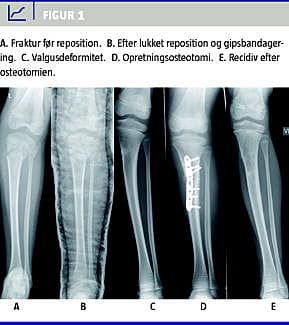

Udfaldet af korrigerende osteotomi er ofte skuffende, idet der er betydelig risiko for recidiv af valgusfejlstillingen [2, 13, 16, 18-20] (Figur 1 ). Desuden er der risiko for komplikationer i form af kompartmentsyndrom og neurovaskulær skade [20].